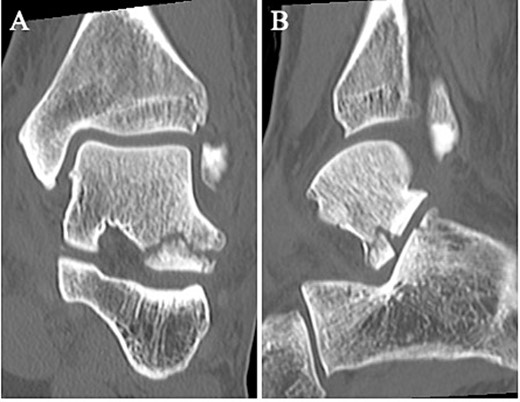

A 24-year-old male basketball player presented to our hospital complaining of left lateral ankle pain during a cutting motion. His height, weight, and body mass index were 172 cm, 64.0 kg, and 21.6 kg/m2, respectively, and he had no history of previous medical conditions. On his first visit to our hospital, he could not walk due to pain. Physical examination revealed swelling, ecchymosis, and tenderness at the lateral aspect of his left ankle. The American Orthopedic Foot and Ankle Society (AOFAS) score was 32 out of 100 points. Plain radiographs of the left ankle showed no abnormal findings in the anteroposterior view, but a fracture line was discovered at the base of the lateral process of the talus in the lateral view (Fig. 1). Non-contrast computed tomography (CT) showed a simple fracture line that extending from the talofibular articular surface down to the posterior talocalcaneal articular surface of the subtalar joint. In addition, the bone fragment was displaced >2 mm (Fig. 2). The patient was diagnosed with Type I LPFT and underwent surgical treatment.

Non-contrast CT showed a simple fracture line that extending from the talofibular articular surface down to the posterior talocalcaneal articular surface of the subtalar joint in the coronal (A) and sagittal (B) views.